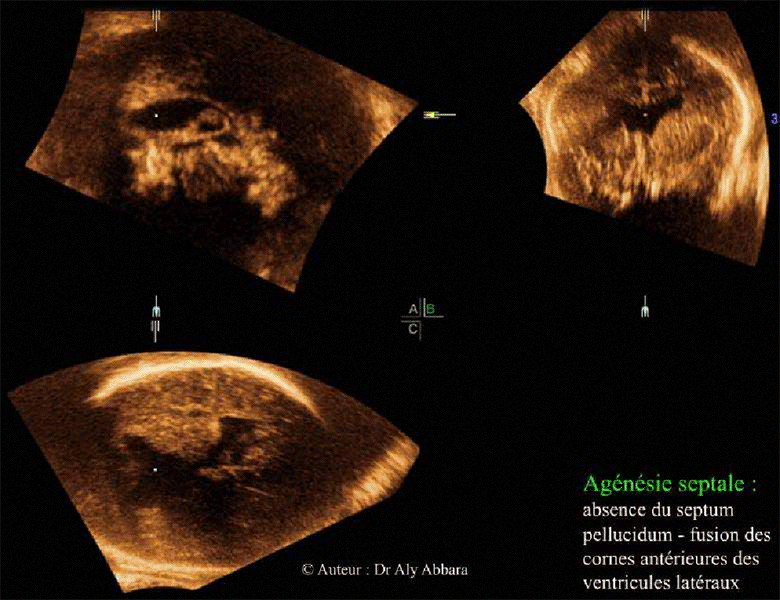

Agénésie septale totale - Foetus de 34 SA

Agénésie septale caractérisée par l'absence du septum pellucidum et la fusion des

cornes antérieures des ventricules latéraux

Images échographiques en trois coupes : axiale, coronale et sagittale médiane